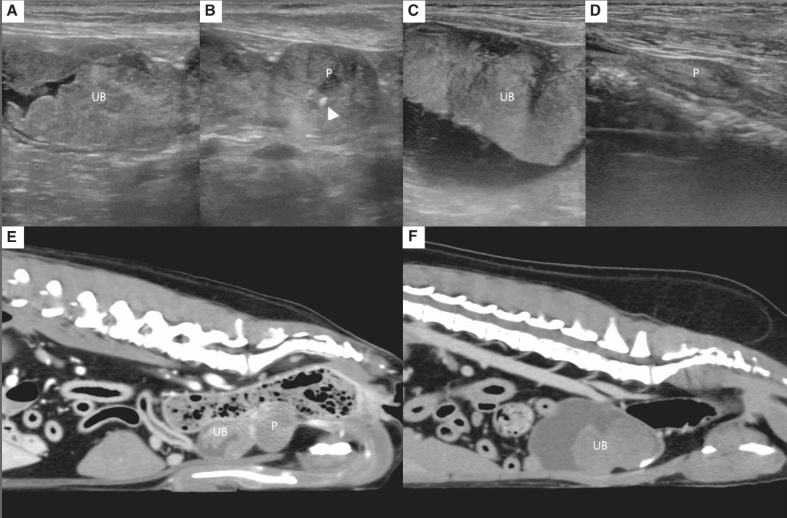

그러면서 면역매개성 사구체신염(ICGN), 변비, 요독증, CKD 관련 미네랄골질환(Mineral Bone Disorder) 등 삶의 질에 영향을 미치는 합병증의 진단과 치료 전략을 소개했다.